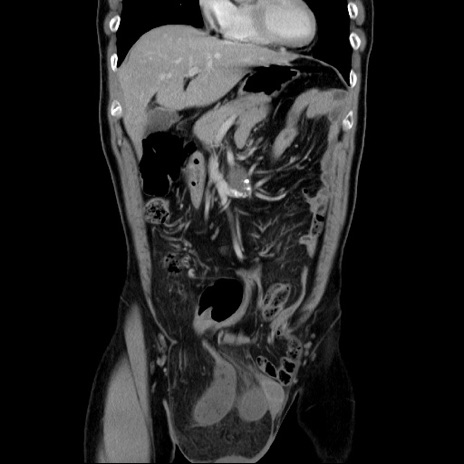

症例34(冠状断像)

【症例】60歳代 男性

【主訴】右鼠径部膨隆

【現病歴】1年程前より右鼠径部膨隆あり。自己にて還納可能だったため放置していた。3時間前より右鼠径部の脱出を認め、還納困難となり受診。

【既往歴】高血圧

【身体所見】右鼠径部に小児頭大の膨隆あり。弾性硬であり、用手還納は困難。左鼠径部にも膨隆を認める。脱出はなし。